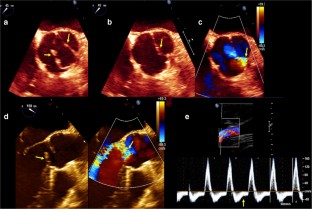

Transesophageal echo long-axis view with and without color Doppler showing thickened aortic cusps and malcoaptation secondary to a flail right aortic cusp. There is severe aortic regurgitation with an eccentric regurgitant jet directed towards the anterior mitral leaflet. (AVI 6084 kb)

Transesophageal echo long-axis view showing malcoaptation of the aortic valve cusps secondary to severe dilation of the aortic root and ascending aorta. (AVI 14969 kb)

Color Doppler from the same patient as in video 2 showing severe aortic regurgitation (AR). Note the large flow convergence and vena contracta as well as the regurgitant jet which fills most of the left ventricular outflow tract, all consistent with severe AR. (AVI 8915 kb)